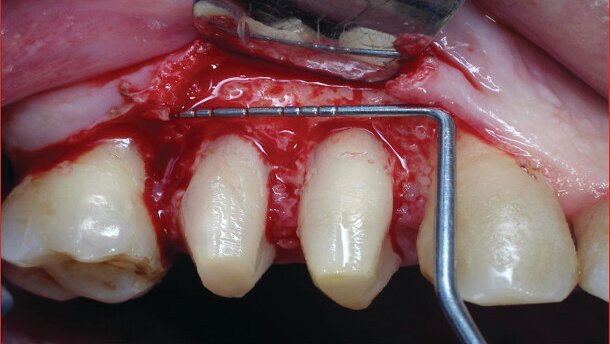

All five implants were placed in one sitting (Fig. 2). Crown lengthening was performed three weeks postop (Fig. 3). Laser operating parameters employed for the various surgical stages were as follows:

With the assistance of a diode laser operating at a power setting of 2.4 W in contact mode, the location of the incision was marked (Figs. 4 and 5). An incision was made with the laser (after anaesthesia) at the buccal and palatal side of teeth #14 and 15 (Fig. 6) and a vertical incision was not required. The buccal and palatal flaps were lifted and the area was explored (Fig. 7); there was soft tissue around the neck of the teeth. The soft tissue was ablated using the laser. Vaporization of soft/granulation tissue (if any exists) after raising a flap is efficient with the Er:YAG laser, offering a lower risk of overheating the bone than that posed by the diode or CO2 lasers23 and often obviates the need for hand instruments. Results from both controlled clinical and basic studies have pointed to the high potential of the Er:YAG laser and its excellent ability to effectively ablate soft tissue without producing major thermal side effects to adjacent tissue have been demonstrated in numerous studies.(16-18)

The Er:YAG laser was aimed at the surface of the exposed bone which was ablated in non-contact mode (Fig. 8). Studies have shown that Er:YAG laser energy effects on bone include bacterial reduction.(22) Following this, all accessible bone surfaces were exposed to laser energy to ablate necrotic bone and to shape and remodel the surface in accordance with established clinical protocols.(13,15,20) The bone level around teeth #14 and 15 fits to the bone level of teeth #13 and 16 (Fig. 9). The mucoperiosteal flap was re-positioned and sutured with silk 3-0, paying particular attention to primary closure of the flap (Fig. 10).